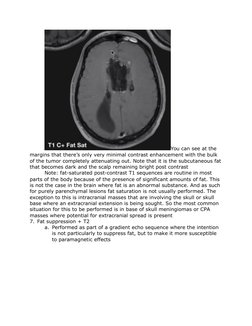

You can see at the

margins that theres only very minimal contrast enhancement with the bulk

of the tumor completely attenuating out. Note that it is the subcutaneous fat

that becomes dark and the scalp remaining bright post contrast

Note: fat-saturated post-contrast T1 sequences are routine in most

parts of the body because of the presence of significant amounts of fat. This

is not the case in the brain where fat is an abnormal substance. And as such

for purely parenchymal lesions fat saturation is not usually performed. The

exception to this is intracranial masses that are involving the skull or skull

base where an extracranial extension is being sought. So the most common

situation for this to be performed is in base of skull meningiomas or CPA

masses where potential for extracranial spread is present